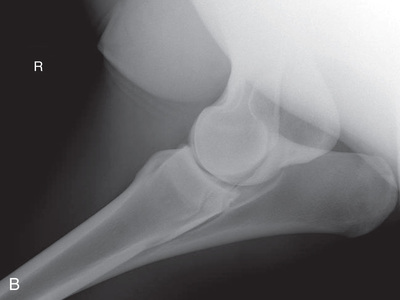

| Stifle | Lateromedial (LM) | Lateral (L) |

| Caudoproximal-craniodistal (CdPr-CrDi) | Caudocranial (CdCr) | |

| Optional stifle | Cranioproximal-caudodistal (CrPr-CdDi) | Craniocaudal (CrCd) |

| Cranioproximal-craniodistal oblique(CrPr-CrDiO) | Skyline patella | |

Radiography of the femorotibial joint (stifle) is difficult because of the thickness of the surrounding tissue and the sensitive nature of this region. Because of the depth of the muscle in the femoral region, the caudocranial projection demonstrates little above the joint space. Radiographs of this region should be attempted only if the patient is cooperative. Safety is paramount in radiography of the hind region of the horse. Sedation or a twitch may be used; general anesthesia is also to be considered.